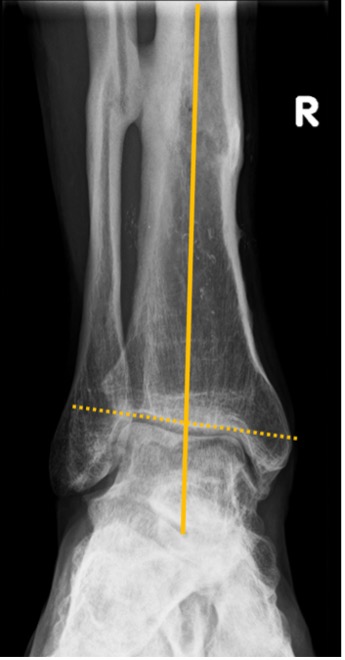

Figure 5. Measuring the deformity

- MDTA (TAS) is crucial for quantifying the supramalleolar deformity (Fig. 3)

- TTA normally defines the centre of rotation of angulation (CORA)

- Talar tilt should be used for quantitative assessment of an intra-articular deformity in the coronal plane. It is defined as the difference between the MDTA and the TTA

Talus tilt (TTA) = TTS – mDTAA

- Values of >4° are considered to be pathological